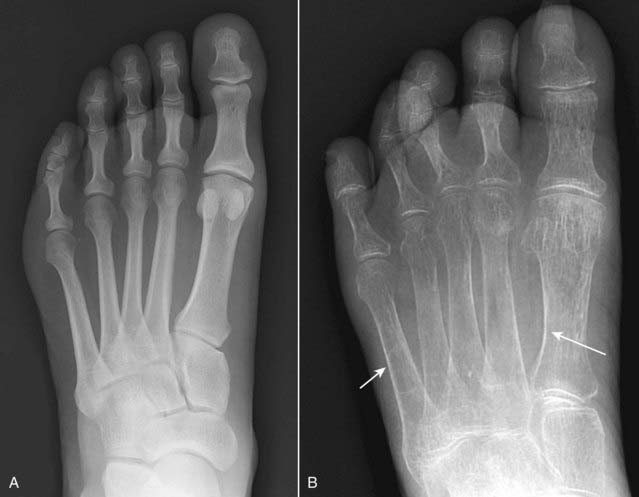

image

Figure 21-13 Normal and osteoporotic foot.

Normal frontal view of the foot (A) to contrast with (B), which shows overall decreased density of the bone and thinning of the cortices (solid white arrows) secondary to disuse osteoporosis. Conventional radiographs are insensitive in diagnosing osteoporosis, and they are subject to technical variations that can mimic the disease even in a healthy individual. More sensitive methods, such as a DEXA scan, should be used to confirm the diagnosis.